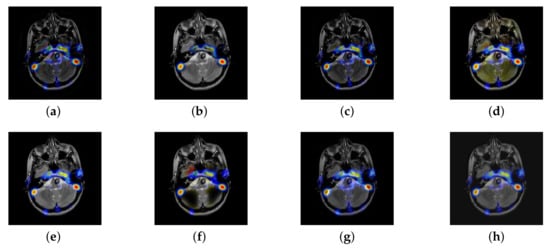

In this section, there are four multi-modal image sets and each set is consist of MRI image and SPECT image that are corresponding to the sanme location slice of the brain as shown in Figure 7. Among them, Figure 7e,f are captured from patients who have suffered a subacute stroke. Figure 7a–d,g,h are captured from patients who have brain tumor. The fused images with different fusion methods based on DTCWT, NSCT, GFF, LPSR, IGM, DDcGAN, FusionCNN, and the proposed methods are shown in Figure 8, Figure 9, Figure 10 and Figure 11. It can be seen that the fused images obtained by LPSR and FusionCNN algorithm have serious color distortion. Based on DTCWT and NSCT algorithm, the fusion image structure information is not obvious. The fused images obtained by GFF and IGM algorithm contain almost no color information, which is not conducive for doctors to make correct diagnosis. The image obtained by the DDcGAN algorithm saves the color information in the SPECT to a great extent; however, the brightness of the fused image is too large, which causes the image to have no sense of hierarchy and the contrast to decrease. By comparing with other algorithms, we find that our algorithm has good color retention effect, clear structure information, moderate brightness, and no artifacts.

Figure 7.

Four pairs of magnetic resonance imaging (MRI)-single-photon emission computed tomography (SPECT) source images: (a,c,e,g) are MRI images; (b,d,f,h) are SPECT images.

Figure 8.

Fused medical images obtained by different algorithms (Figure 7a,b): (a) dual tree complex wavelet transform (DTCWT), (b) guided filtering fusion (GFF), (c) non-subsampled contourlet transform (NSCT), (d) Laplacian pyramid sparse representation (LPSR), (e) internal generative mechanism (IGM), (f) Fusion convolutional neural network based (FusionCNN), (g) dual-discriminator conditional generative adversarial network based (DDcGAN), and (h) FusionNet.